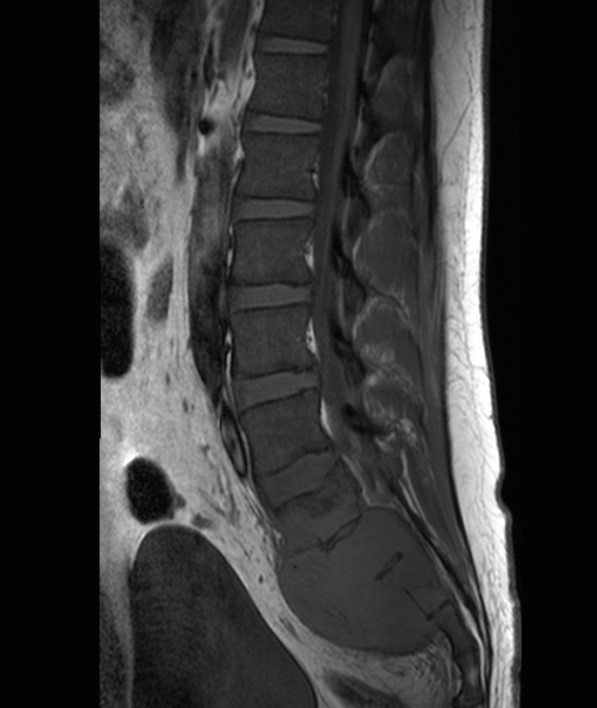

Primary lymphoma of the sacral bone is a rare myeloproliferative disease, occurring mostly after 4th decade of life and mainly in male patients. We reported a case of sacral bone lymphoma in a 24-year-old man with low back pain and radiculopathy. Imaging showed a sacral bone lesion which later proved to be non-Hodgkin’s lymphoma on histopathologic study. Lymphoma of the sacral bone is chemoresponsive and carries a good prognosis. Sacral bone lymphoma should be considered as a differential diagnosis in patients with low back pain who is not responding to analgesic treatment.